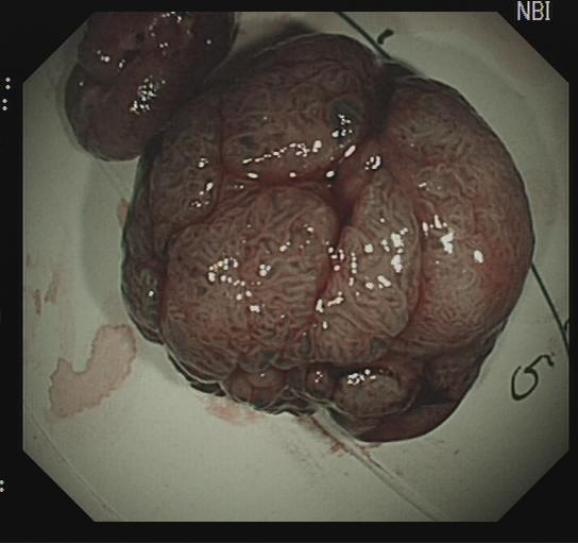

上下滑动查看△图5 大型病变的ESD治疗。